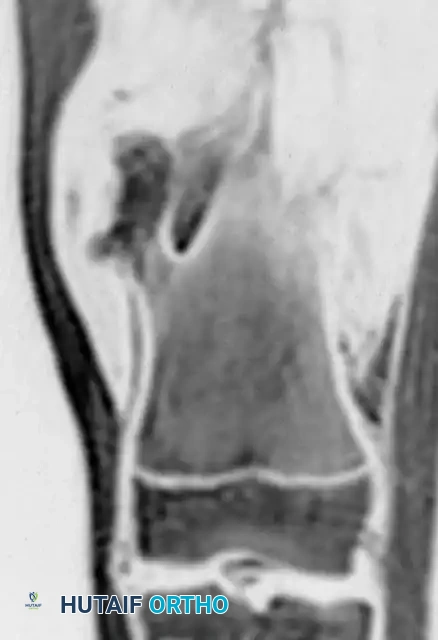

Radiograph of a broad-based, sessile osteochondroma on the distal femur.

MRI of the distal femur sessile lesion.